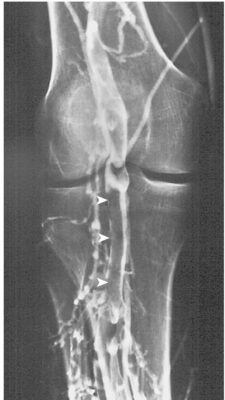

Chụp tĩnh mạch cản quang (Contrast venography):

Là một thăm dò xâm lấn được xem là “tiêu chuẩn vàng” để chẩn đoán DVT. Đây là thăm dò duy nhất có thể phát hiện vị trí DVT một cách đáng tin cậy ở tĩnh mạch bắp chân, tĩnh mạch chậu và tĩnh mạch chủ dưới (Hình). Hạn chế của phương pháp chụp tĩnh mạch là phức tạp về kỹ thuật, cần sử dụng chất cản quang, nguy cơ phản ứng dị ứng và gây khó chịu cho bệnh nhân. Do đó, thăm dò này không được khuyến khích làm thăm dò sàng lọc ban đầu.